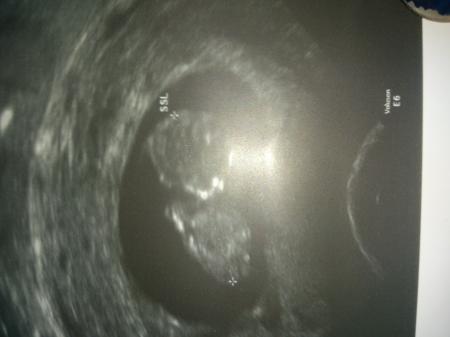

Ich Denk ma sie will nur vergleichen und schauen ob bei ihrem alles normal ist auch wenn der Arzt ein ok gegeben hat. Guck mir auch immer gerne Bilder an zum Vergleich. Also nicht immer gleich das schlimmste denken bitte. Bei dem Bild war ich in der 12 Woche

Bild zu

Denke sweety. Tolles Bild. Natürlich will ich nix böses bin selber bei den September Mama s nur wurde ich zurück gestuft.... 1 Woche.... Und wollte mal vergleichen. Weil ich eigentlich fand im Gegensatz zu vielen anderen wo bei mir im Monat weiter sind sah man bei mir mehr. Kann auch sein weil s einfach meins ist. Mein Bild ist von 5.2 da war er 27 mm groß. Eigentlich wäre ich 11+5 bin aber nun 10+5